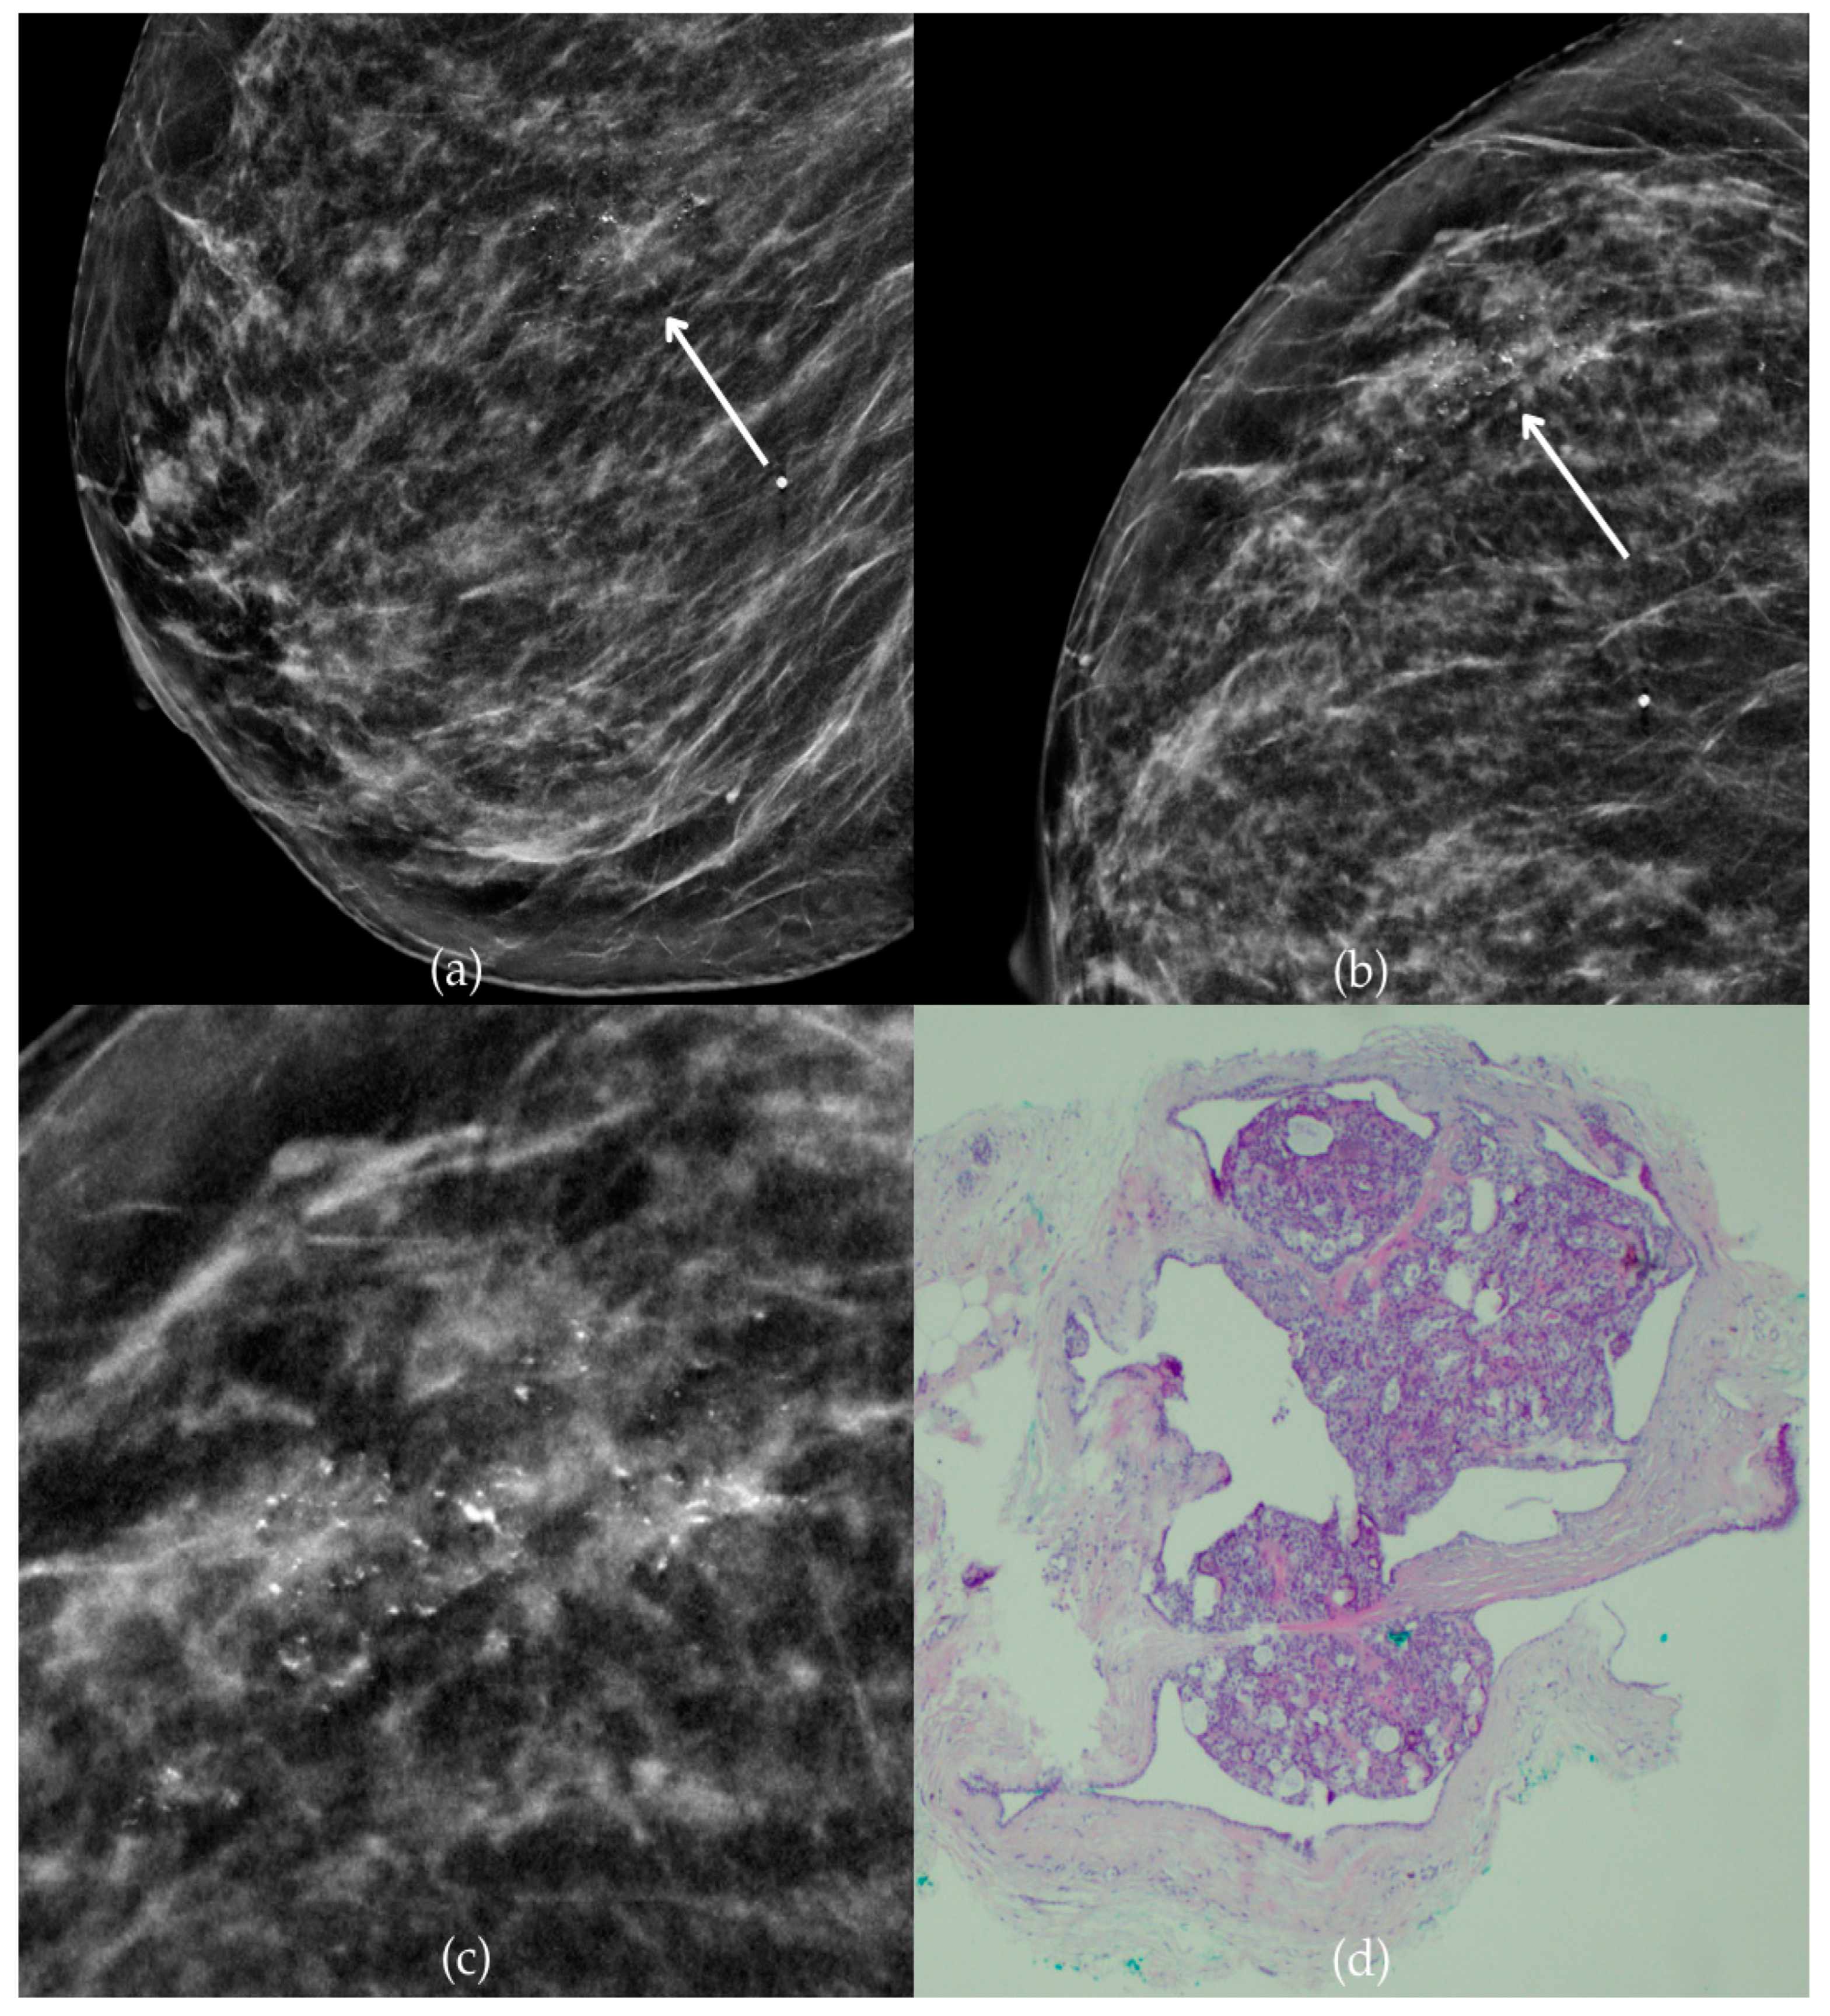

Figure 1 presents mammographic and histopathological images of a 74-year-old patient. The mammogram of the right breast shows grouped coarse heterogeneous and fine pleomorphic calcifications in the upper outer quadrant, classified as a BI-RADS 4 finding. Given the suspicious nature of these findings, a biopsy was performed. A tissue analysis confirmed the presence of a DCIS (category B5a). The patient underwent quadrantectomy, and the postoperative pathology confirmed the diagnosis. At the most recent follow-up, conducted one year after the initial diagnosis, the US examination was classified as BI-RADS 2, indicating benign findings.

Figure 1.

Ductal carcinoma in situ (DCIS). (a) Mediolateral oblique (MLO) mammography view; (b) craniocaudal (CC) mammography view of the right breast showing grouped coarse heterogeneous and fine pleomorphic calcifications (marked with arrows) in the upper outer quadrant. (c) Magnified mammographic image of grouped coarse heterogeneous and fine pleomorphic calcifications. (d) The histopathological image of the biopsy sample reveals the characteristic features of DCIS (HE staining; 40× magnification).